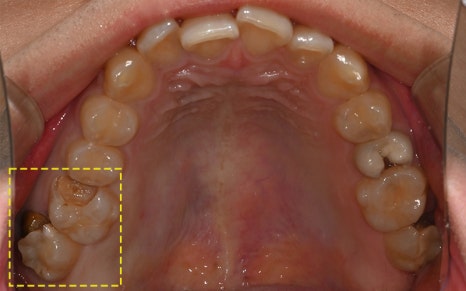

🔷 가장 좋은 임플란트를 선택한 환자분 이야기

2025.05.25

이 환자분은 고작 19세입니다.

어린 나이에 충치로 인해 어금니를 잃고,

임플란트 치료를 결심하게 되었는데요.

하지만 이 환자분에게는

특별한 고민이 필요했습니다.

“아직 너무 어리다.

앞으로 이 임플란트를 수십 년 써야 한다.”

2025.05.31

그래서 저희는 세계에서 가장 오래 쓰이는,

그리고 가장 튼튼하다고 인정받는

스위스 스트라우만 임플란트를 추천드렸고

수술을 진행하였습니다!